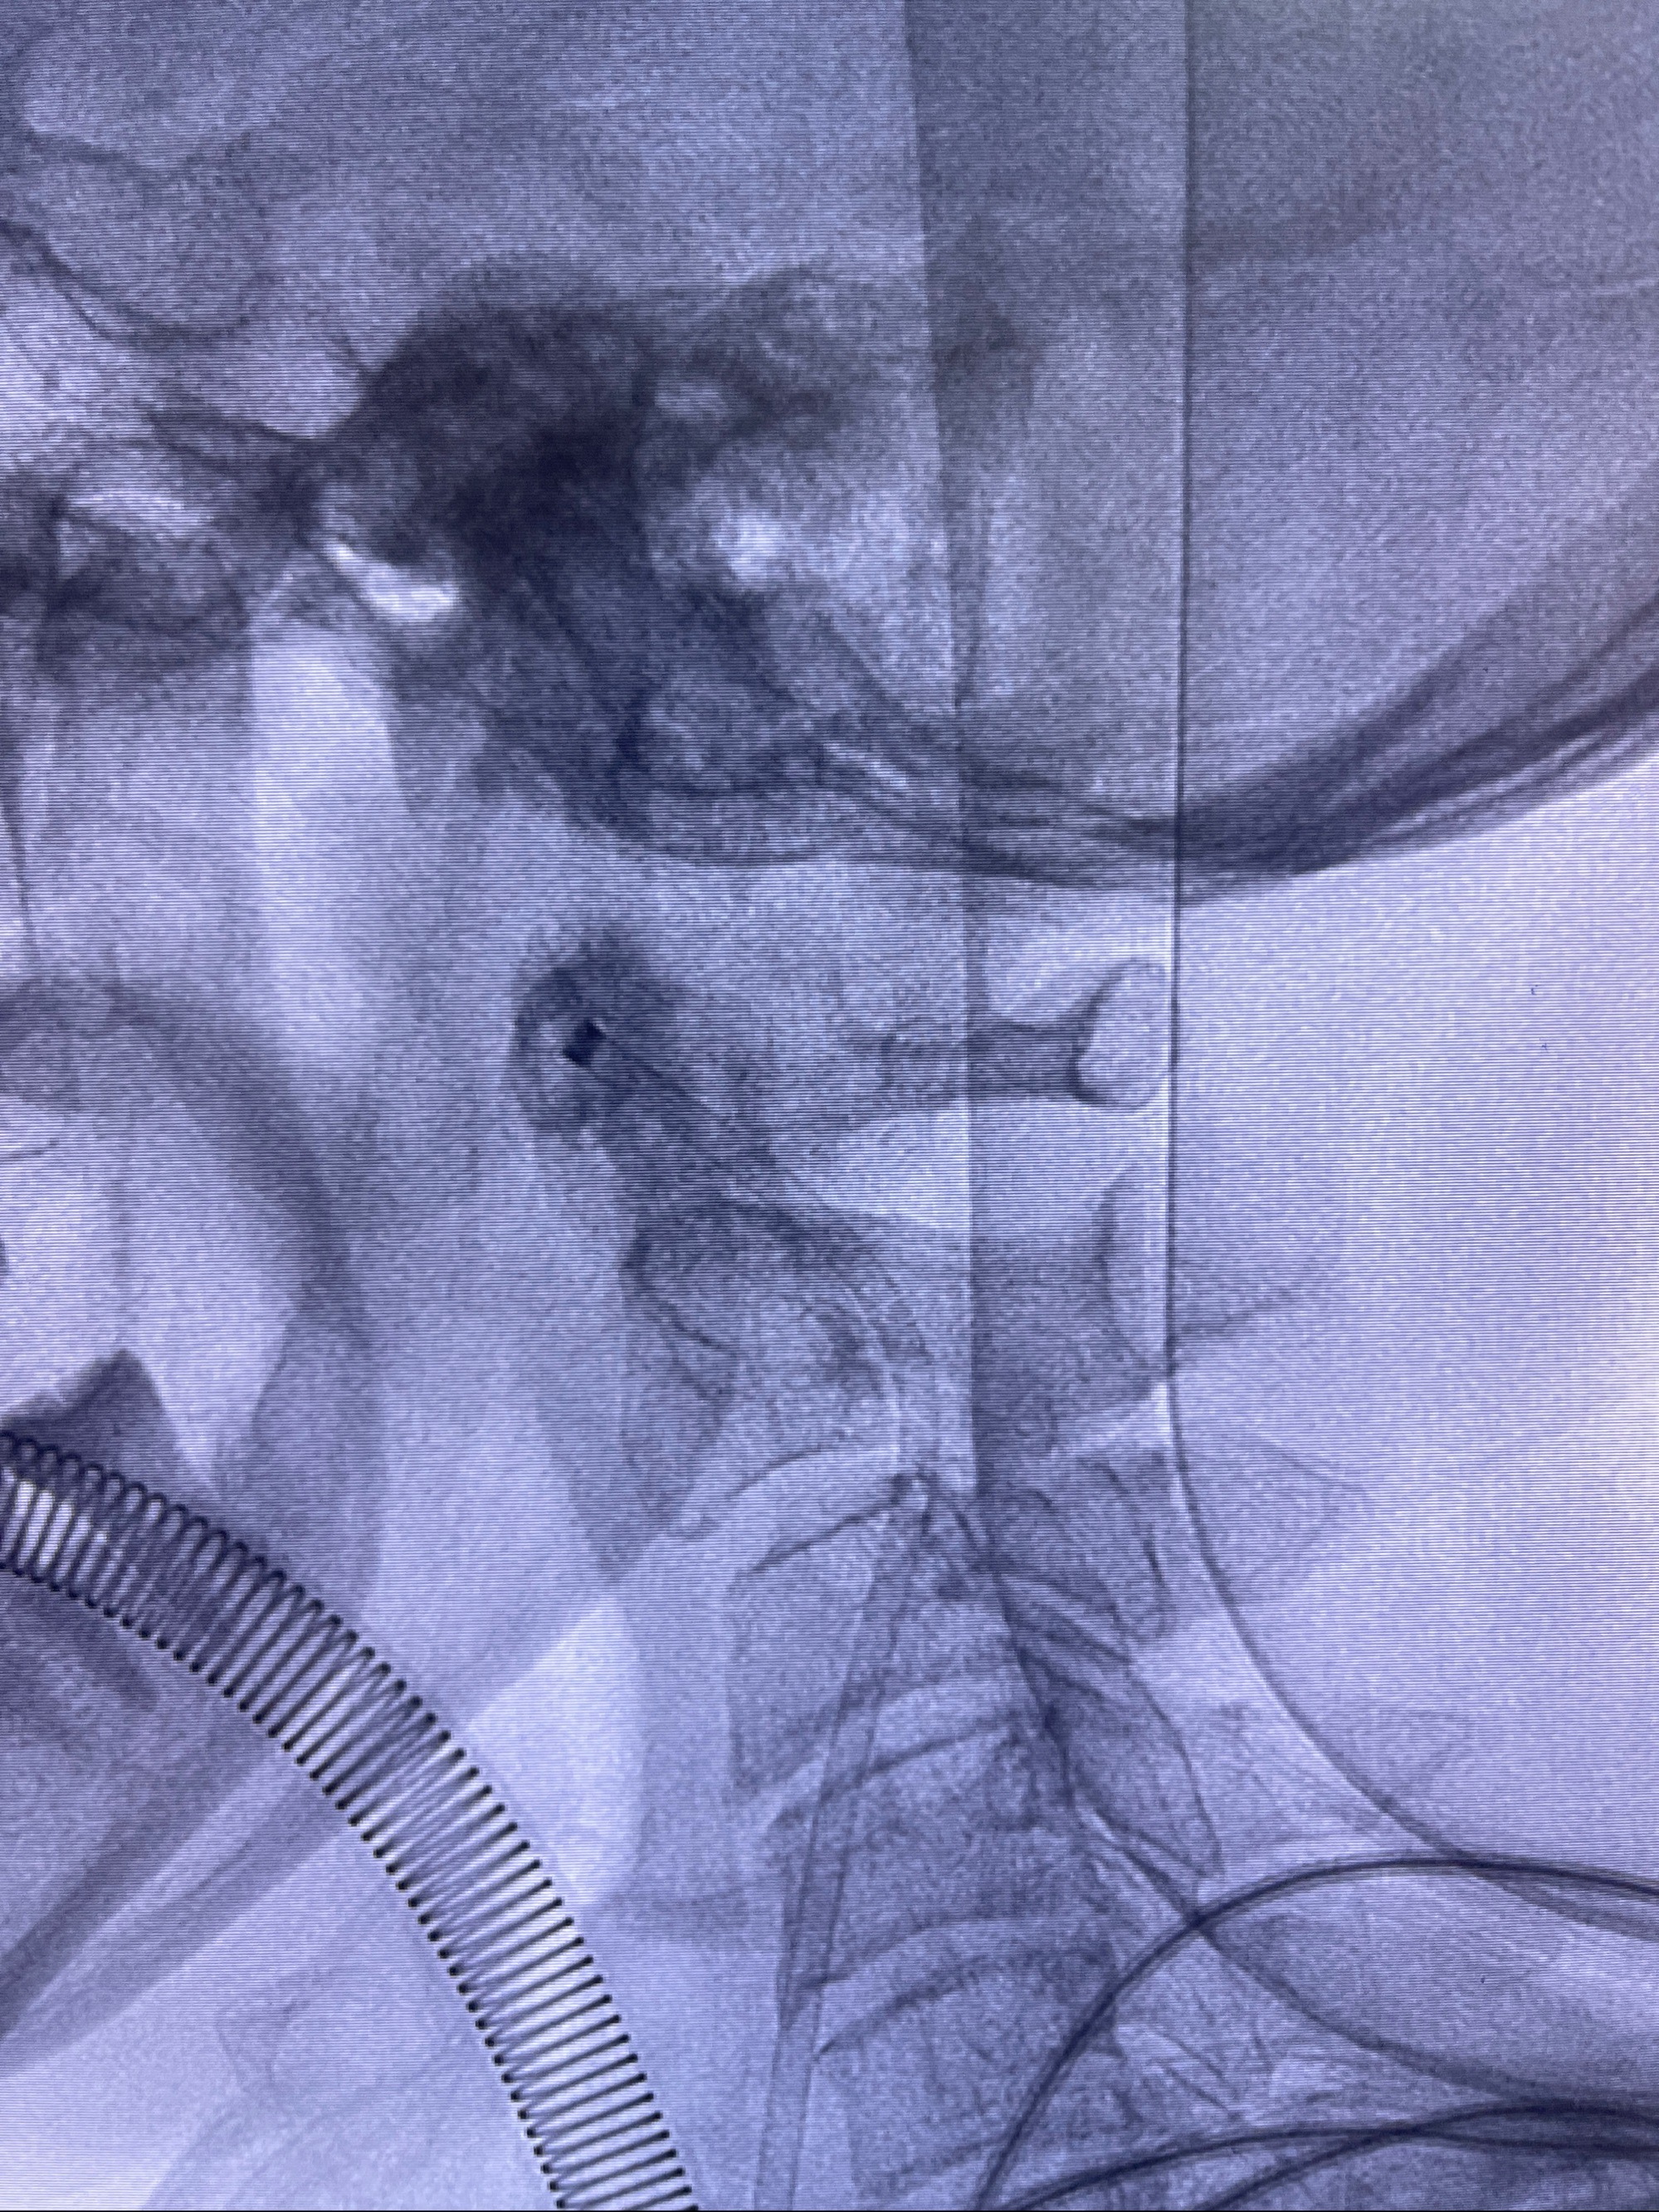

2023-09-06全麻下行左侧颈眼动脉瘤

密网支架辅助栓塞

- 普微森088 90cm导引导管

- 125cmMPA

- 0.035泥鳅导丝

- TB支架导管

- Echelon10 45°角微导管

- Synchro2微导丝

- Tubridge 4.0-20mm密网支架

- 加奇微弹簧圈:7*30/6*20/5*20/2*8